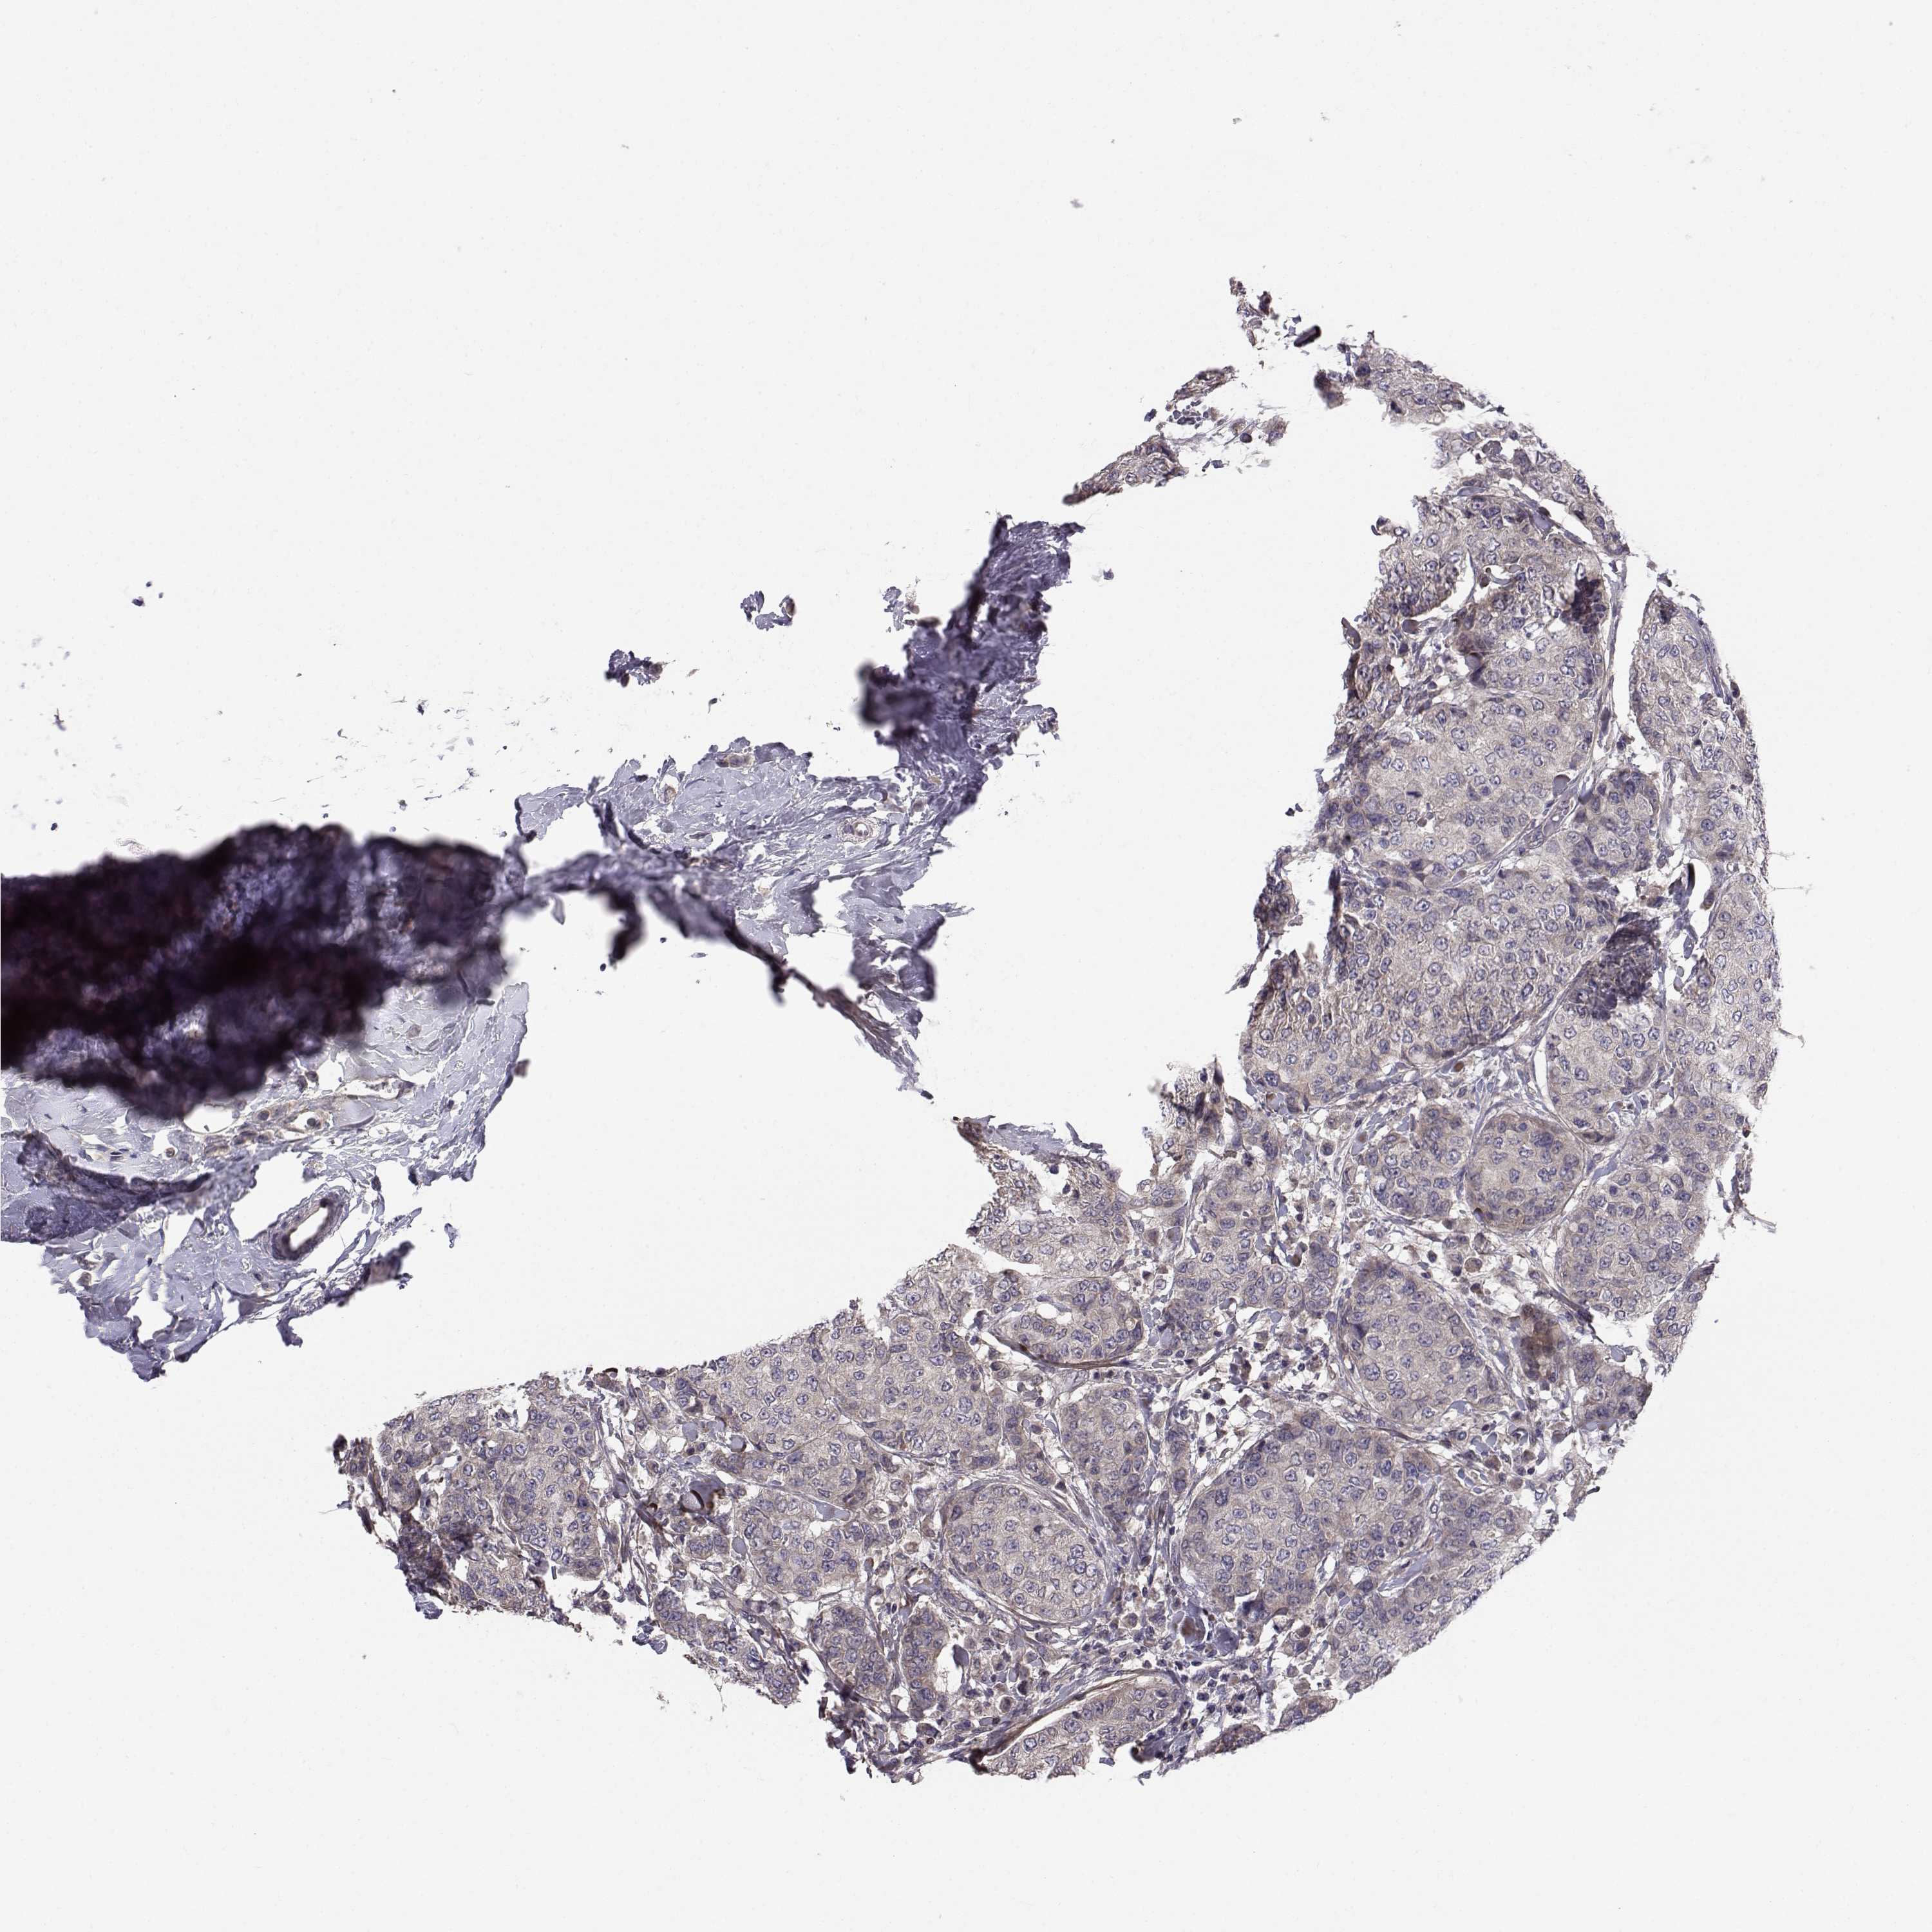

CANCER BREAST CANCER Show tissue menu

BRCA TCGA BRCA VALIDATION PROTEIN EXPRESSION